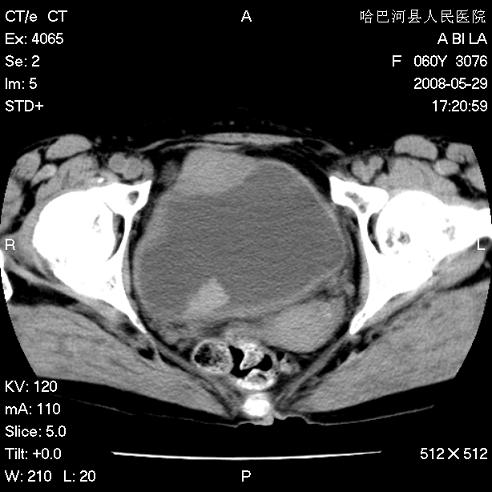

标题: CT13730:排尿不畅4天,抗炎治疗无效,现尿中可见血块 [打印本页]

标题: CT13730:排尿不畅4天,抗炎治疗无效,现尿中可见血块

手术结果及病理:膀胱癌并膀胱壁转移,膀胱内血块